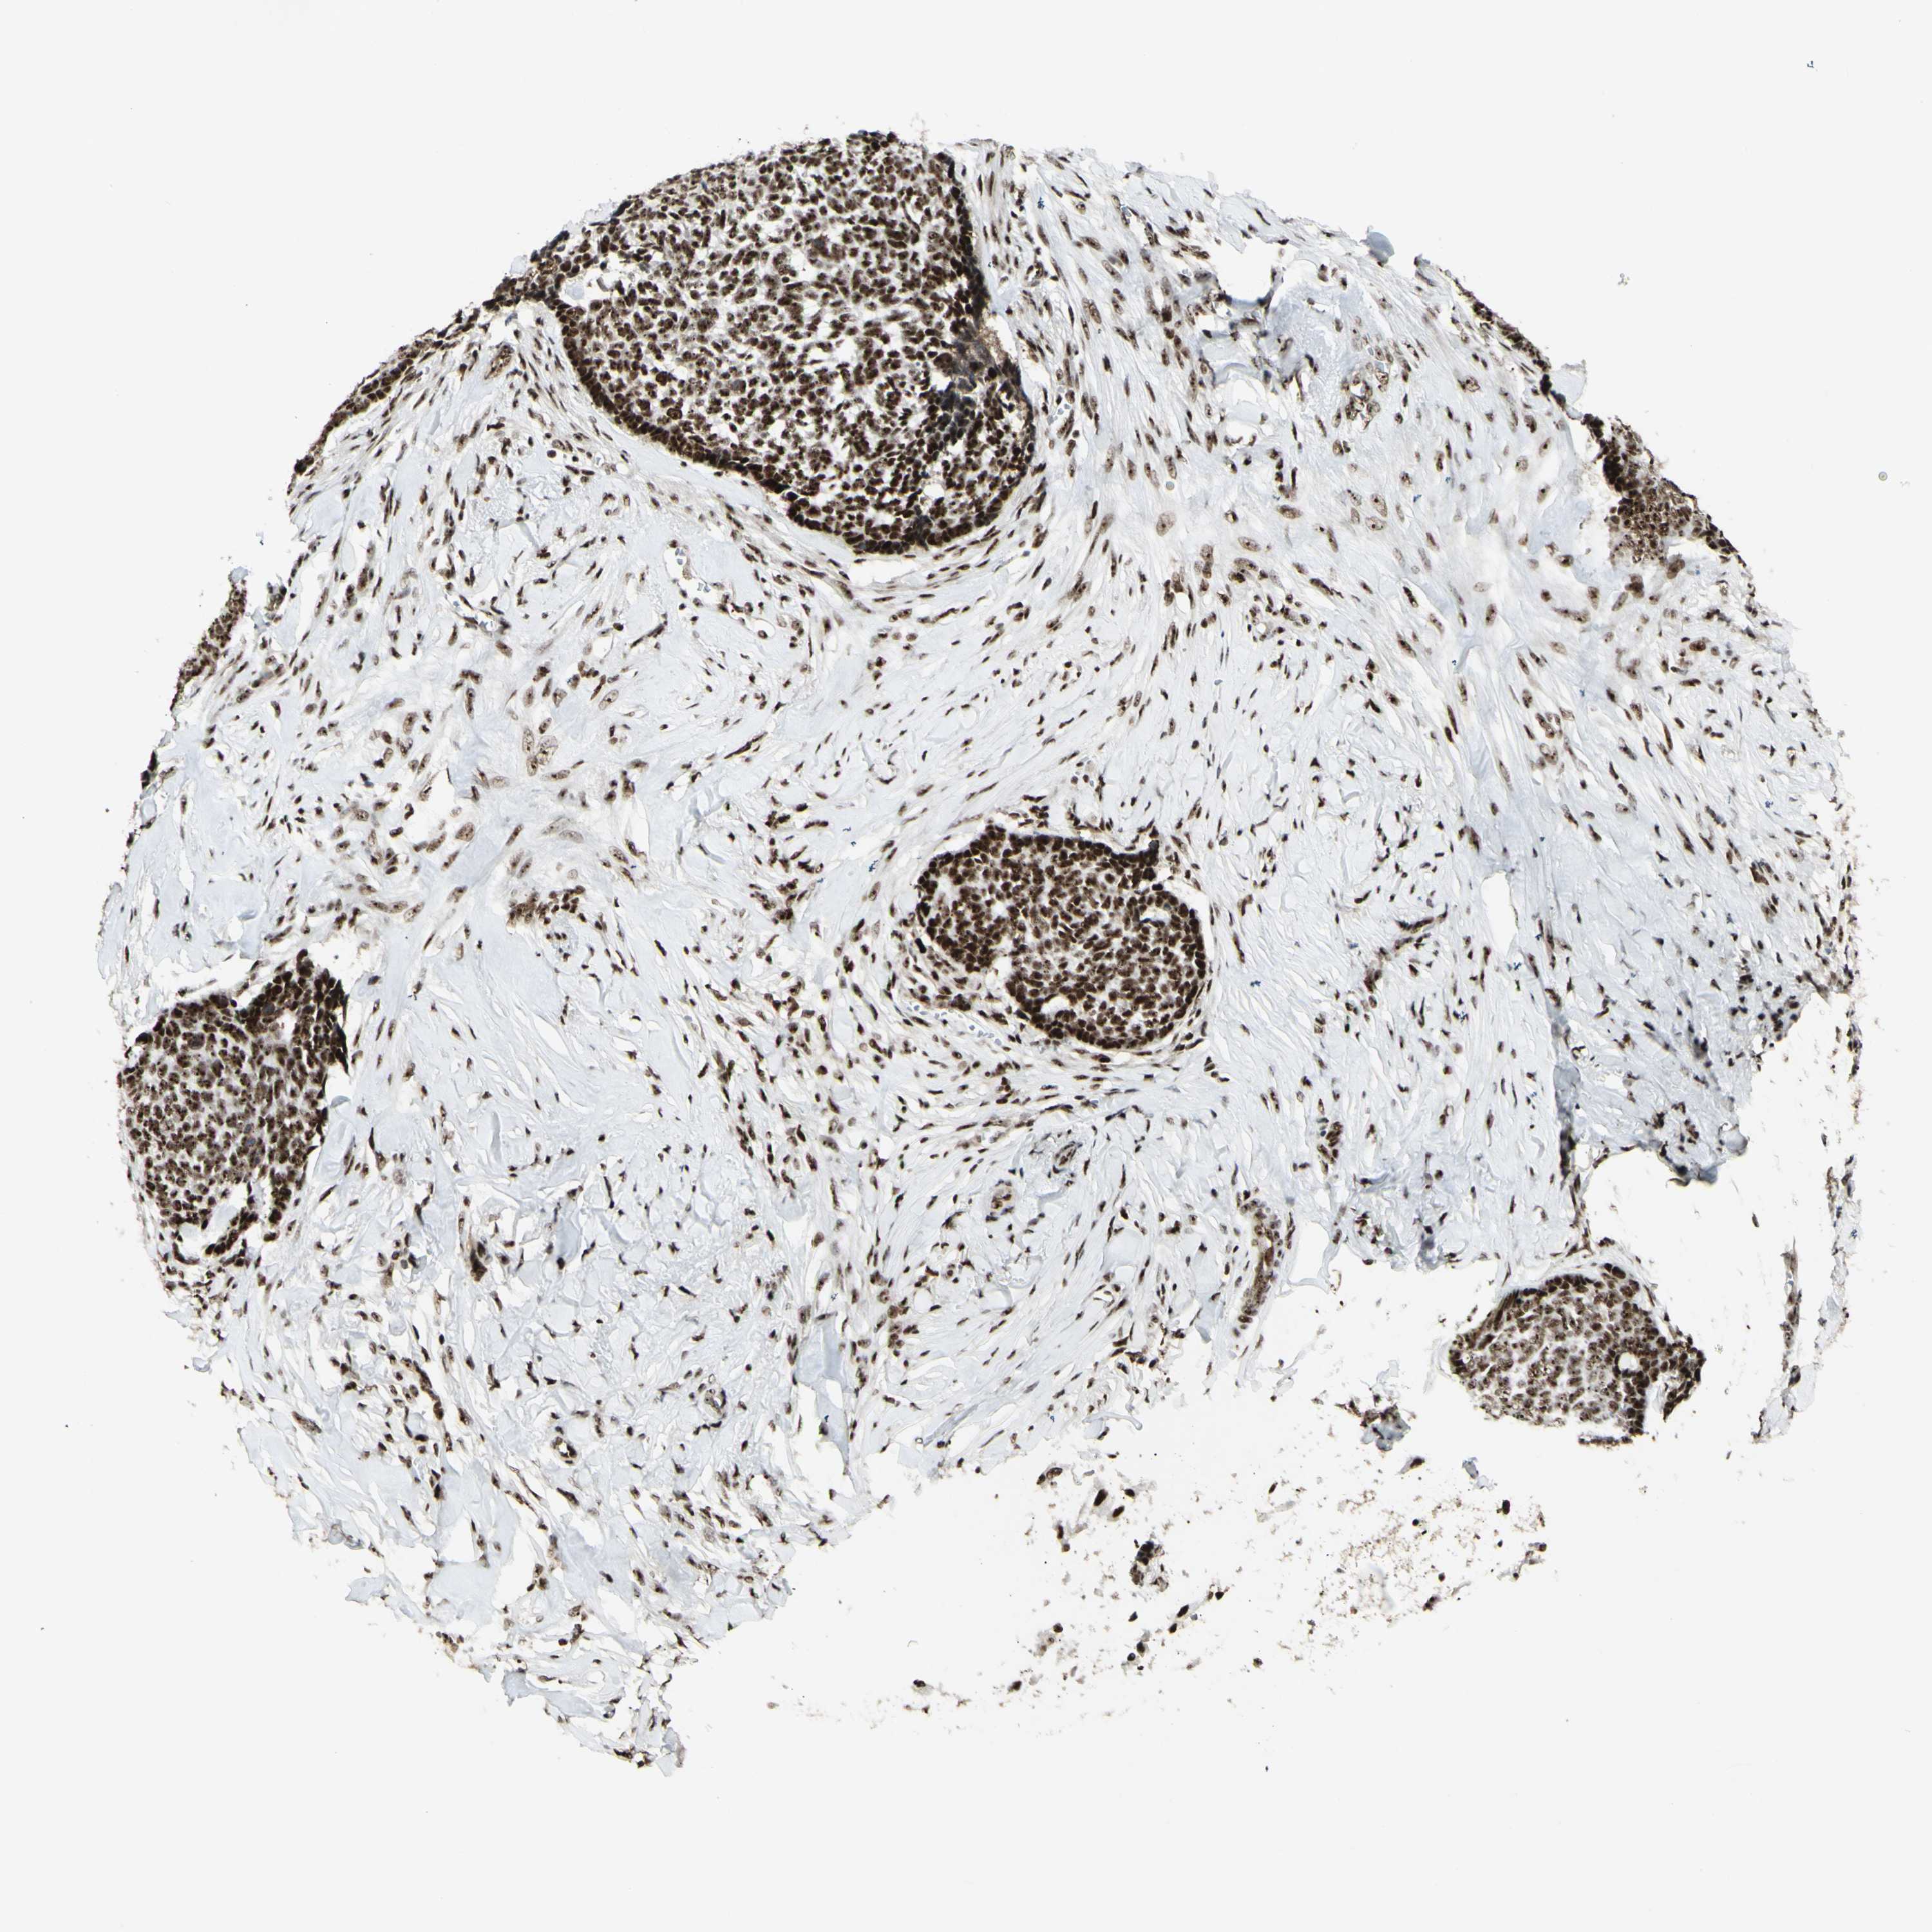

SKIN CANCER - Protein expressioni

A mouse-over function shows sample information and annotation data. Click on an image to view it in a full screen mode. Samples can be filtered based on level of antibody staining by selecting one or several of the following categories: high, medium, low and not detected. The assay and annotation is described here.

Each image is clickable and will lead to virtual microscopy that enables deeper exploration of all samples and also displays staining intensity scores, fraction scores and subcellular localization as well as patient and tissue information for each sample.

Antibody HPA028050

Staining

High

Intensity

Strong

Quantity

>75%

Location

Nuclear

Basal cell carcinoma